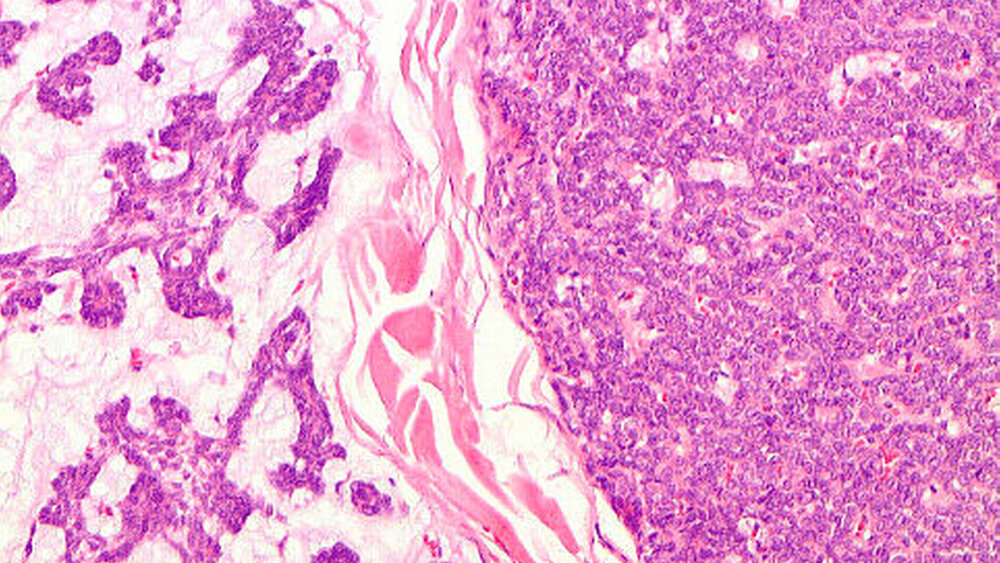

Der histopathologische Befund bestätigte den Verdacht eines pleomorphen Adenoms mit kapselartiger Begrenzung zum umgebenden, strukturell unauffälligem Speicheldrüsenparenchym der linken Glandula parotis (Abbildungen 5 und 6).

Das pleomorphe Adenom ist ein gutartiger Mischtumor der Speicheldrüsen, der sich durch seine strukturelle Pleomorphie auszeichnet. So erscheinen im histopathologischen Bild epitheliale und myoepitheliale Zellen, vermischt mit mucoiden, myxoiden und chondroiden Komponenten [Jain et al., 2015].

Bei fehlender vollständiger Kapsel ist eine klare Abgrenzung zum angrenzenden Gewebe schwierig. Das pleomorphe Adenom ist von gesundem Speicheldrüsengewebe umgeben, welches durch sein Wachstum komprimiert wird [McGurk et al., 1996; Zbären und Stauffer, 2007].